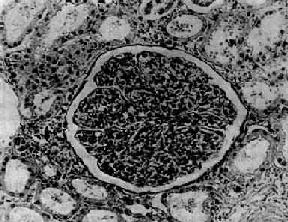

图12-7 弥漫性毛细血管内增生性肾小球肾炎 肾小球内细胞数量增多,系膜细胞和内皮细胞增生并有少量中性白细胞浸润,毛血管腔狭窄 上皮细胞一般无明显增生,少数严重的病例肾小球的壁层和脏层上皮细胞可增生,形成新月体。这种病变容易引起肾小球纤维化。如数量少,对功能影响不大。如病变广泛,可发展为新月体性肾炎。 在电子显微镜下可见肾小球系膜细胞和内皮细胞增生肿胀。基底膜和脏层上皮细胞间有致密物质沉积。这些沉积物大小不等,有的很大,在基底膜表面呈驼峰状或小丘状(图12-8,图12-9)。沉积物表面的上皮细胞足突多消失。基底膜变化不明显有时边缘稍不规则。沉积物一般在发病后几天就可出现,在4~6周内消失。有时基底膜内侧内皮细胞下和系膜内也可见小型沉积物。

一、弥漫性毛细血管内增生性肾小球肾炎弥漫性毛细血管内增生性肾小球肾炎(diffuse endocapillary proliferative glomerulonephritis)病变为弥漫性,两侧肾几乎全部肾小球皆受累。这种肾炎常发生于感染以后,故有感染后肾小球肾炎之称。最常见的为A组乙型溶血性链球菌感染,其中以12型、4型、1型及49型与肾炎的关系最为密切。一般发生在链球菌感染后1~3周,是链球菌感染引起的变态反应性疾病,称为链球菌感染后肾炎。除链球菌外,其他细菌如葡萄球菌、肺炎球菌和某些病毒及寄生虫等也可引起这种类型的肾炎。这种肾炎多见于儿童,成人也可发生,但病变往往比儿童严重。一般发病较急,临床主要表现为急性肾炎综合征。 【病理变化】 病变为弥漫性,两侧肾同时受累。病变进展较快,主要变化为肾小球内细胞增生。早期,肾小球毛细血管充血,内皮细胞和系膜细胞肿胀增生并有少量中性粒细胞浸润。毛细血管通透性增加,血浆蛋白质可以滤过而进入肾球囊。因此,病人的尿液中常有蛋白、红细胞及白细胞。轻型病人,病变可不再发展,以后逐渐痊愈;比较严重的病例,病变继续发展,肾小球内细胞增生加重。增生的细胞主要为系膜细胞和内皮细胞。增生细胞压迫毛细血管,使毛细血管腔狭窄甚至闭塞,肾小球呈缺血状(图12-7)。此外,肾小球内有多数炎性细胞浸润,主要为中性粒细胞,有时并有少数嗜酸性粒细胞、单核细胞、红细胞、浆液和纤维素性渗出液。镜下,肾小球内细胞数量增多,肾小球体积增大。病变严重时,毛细血管腔内可有血栓形成,毛细血管壁可发生纤维素样坏死。坏死的毛细血管袢破裂出血,大量红细胞进入肾球囊及肾小管腔内,可以引起明显的血尿。不同的病例病变表现形式可能不同。有的以渗出为主,称为急性渗出性肾小球肾炎。有些病变严重,肾小球毛细血管袢坏死,有大量出血者称为出血性肾小球肾炎。